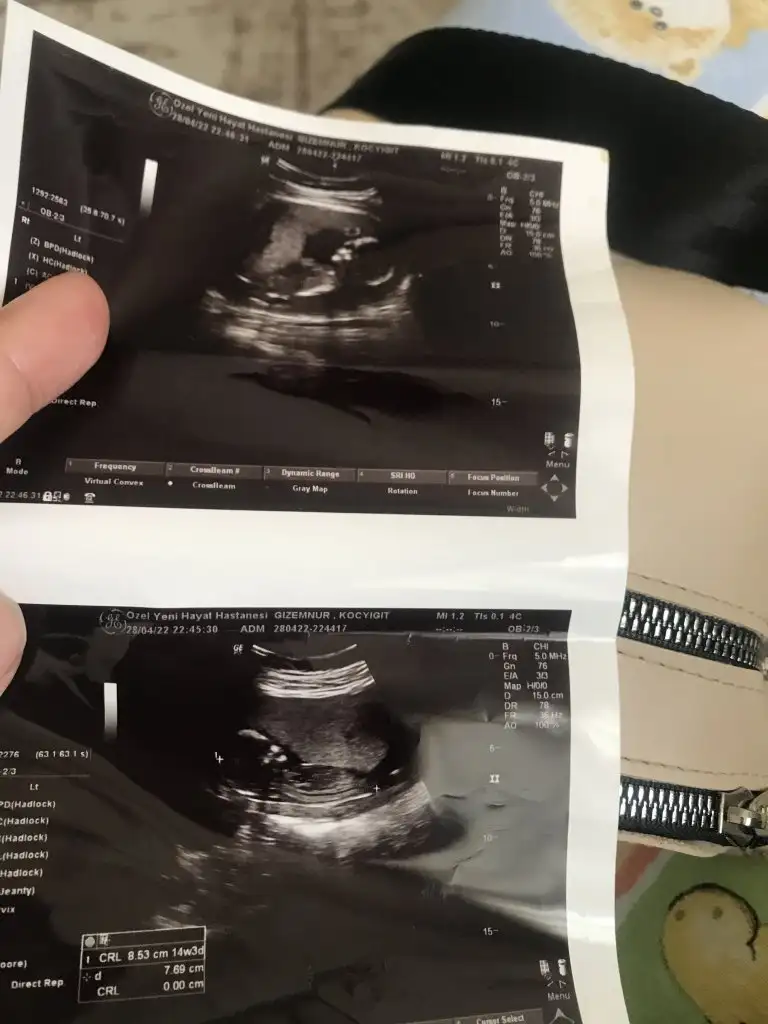

Randevu saatinde oradaydık doktor bebeğe baktı ve suyunun çok az olduğunu bebeğin haraketlerinin çok kısıtlı olduğunu söyledi. İnanamadım dalga geçiyo sandım dünyam başıma yıkıldı resmen eşimle şok geçirdik. Ordan çıktım ve doktorumu aradım ağlayarak hemen gel dedi. Gittim muayene etti bebeğin suyunda bi azalma var ama amacının 28. Haftalara kadar götürmek olduğunu yaşayabileceğini ama kalbininde durabileceğini söyledi. Yani şuan için her şey Allahtan…

Çok teşekkür ederim Allah razı olsun hepinizden maalesef bebeğimin böbrek ve idrar kesesini göremedik, yani doğuştan yok. Bu yüzden içtiği suyu işiyemiyor ve su oluşmuyor. Çok minik ihtimal biz göremeyebiliriz su tekrardan oluşabilir dedi Buda bi mucize olurmuş 30 yılda 2 kere denk geldi sadece dedi. Perşembe günü üniversite hastanesine yönlendirdi bebeğin suyuna tekrar bakılıp kurul toplanacak oluşmadıysa malesef yapacak bişey yok. Buda bizim sınavımız dilerim kimse yaşamasın ve herkes sağlıcakla alsın kucağına inşallah.Çok çok üzüldüm Allah yardımcınız olsun Allah şafi ismiyle şifa versin.